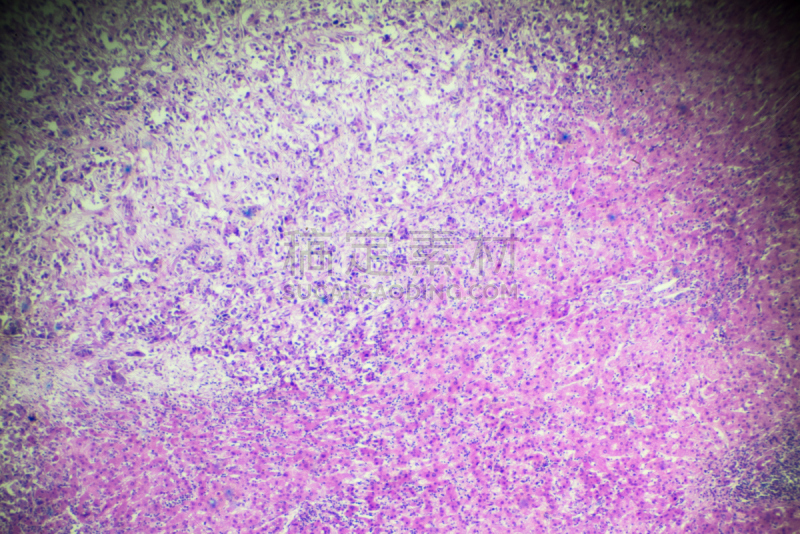

详情

JPG